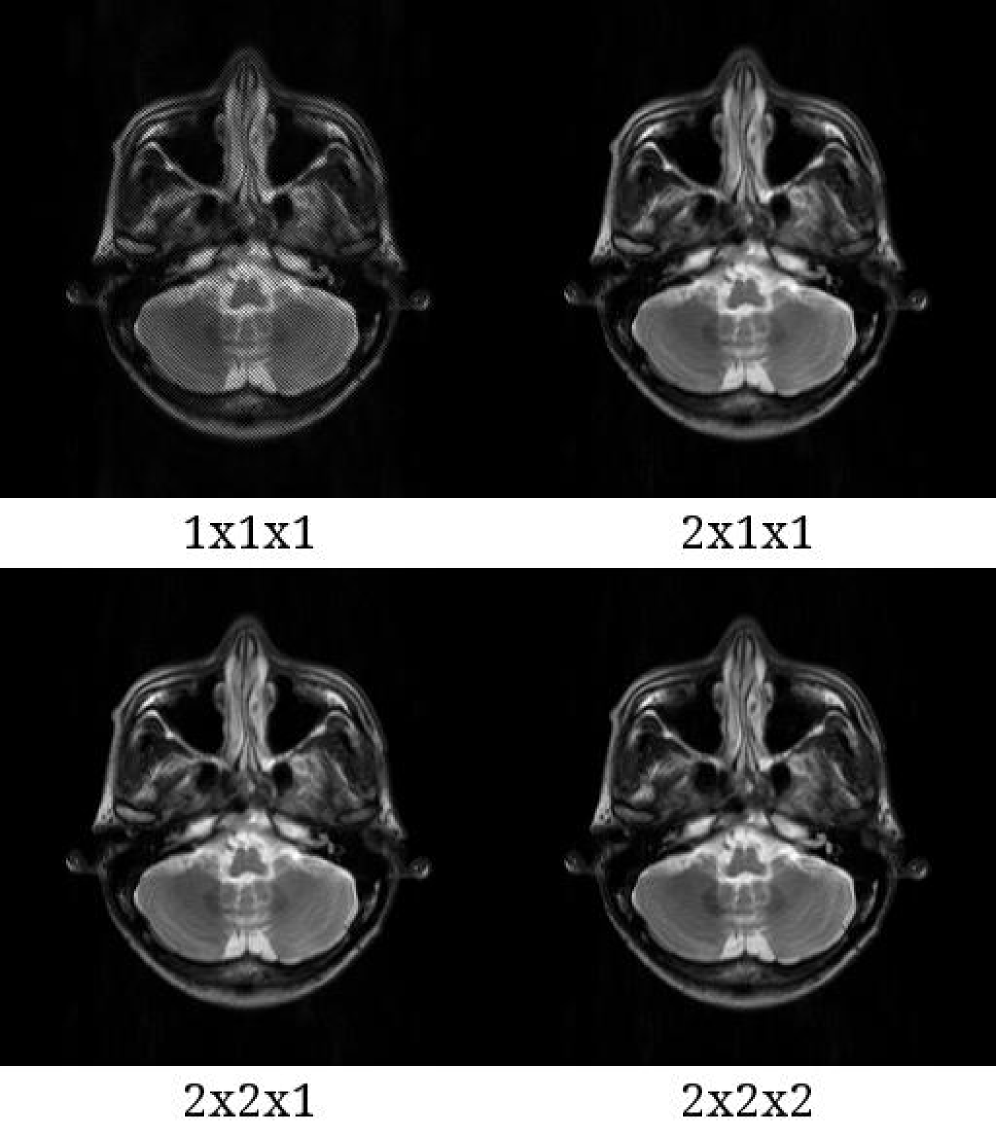

[Uncaptioned image]

Figure S2. Reconstructed images and their error images in the case of a T2W sequence. (a) Reconstructed images using the brain phantom with reference (ungrouped), 64 clusters, 128 clusters and 256 clusters. (b) Errors between the reference and grouped images. The errors were multiplied by 10. As shown in the error images, the image with 256 clusters were visually close to the reference image. Abbreviations: T2W, T2-weighted.